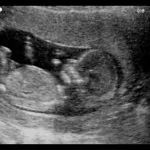

आठव्या आठवड्यातील अल्ट्रासाऊंडमध्ये तुम्हाला काय दिसू शकते?

८ आठवड्यात गर्भ कसा दिसतो

- डोळे पुढच्या बाजूला स्थिर

- बाळाची डोक्यापासून पायापर्यंतची लांबी २.३ सेमी

- कान तयार होऊ लागतील

- तुमचे बाळ कोपर हलवू शकते

- बोटे लहान कळ्यांसारखी दिसतात

- पचनसंस्थेचा विकास होऊ लागतो

- बाळाचे डोके अजूनही त्याच्या पोटाच्या दिशेने झुकलेले आहे